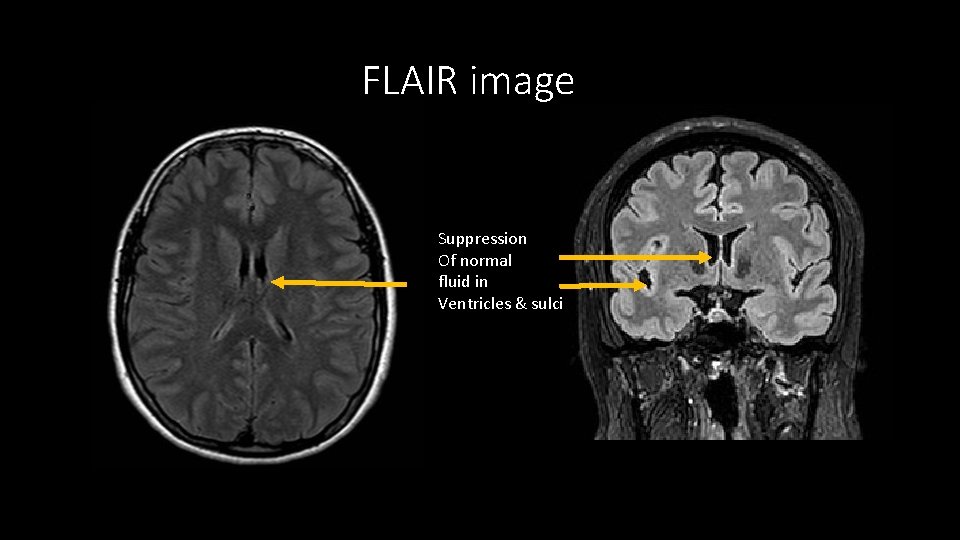

FLAIR (fluid-attenuated inversion recovery) • Sensitive but not specific • a type of T 2 but CSF is black. • FLAIR: Helps identify pathologies. shows areas next to CSF (periventricular) very well. Also good for juxtacortical areas. • Inferior quality to other sequences in posterior fossa and spinal cord.

FLAIR • Helps differentiate VR space from Lacunar infarct • Causes of FLAIR hyperintensity in sulci SAH High protein (meningitis, neoplastic) High oxygen tension (intubation & ventilation) Artifact.

FLAIR image Suppression Of normal fluid in Ventricles & sulci